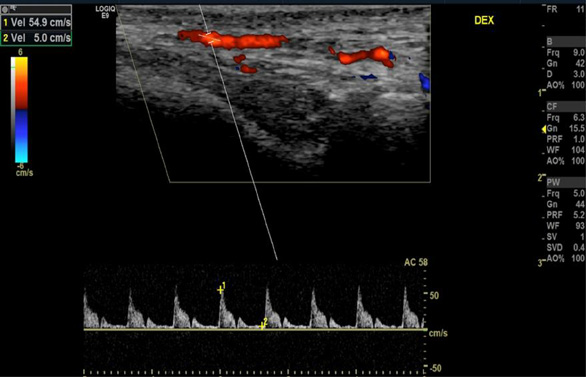

Five years later, at the follow-up visit, the patient did not feel any pain or discomfort in the temporal area bilaterally. No inflammatory signs of temporal arteries were detected (Fig. 3). The control color-coded duplex sonography showed no halo sign, and normal blood flow velocities were registered (Fig. 4). It was concluded that there were no clinical or ultrasound signs of temporal vasculitis.

Normal blood flow velocities of the right (A) and left (B) superficial temporal arteries were observed without the ‘halo’ sign.